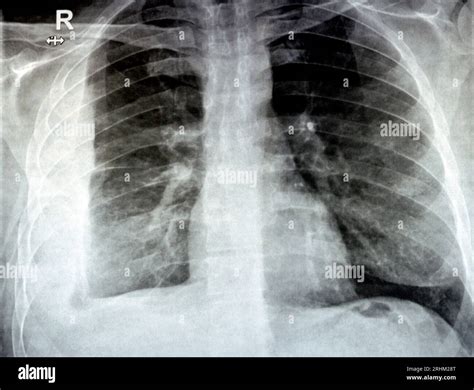

How Pneumonia Appears on an X-ray

Healthy lungs appear mostly black on an X-ray because they are filled with air. When pneumonia is present, the areas of the lung affected by the infection appear as opaque, white, or cloudy patches. This phenomenon is known as consolidation. It occurs because the air in the alveoli has been displaced by fluid, inflammatory cells, or debris, which blocks the passage of X-rays.

• Bronchopneumonia: This presents as patchy, diffuse opacities scattered throughout both lungs, rather than being confined to one area.

• Interstitial Pneumonia: Often caused by viral infections, this shows up as fine, lace-like markings or reticular patterns rather than dense consolidation.